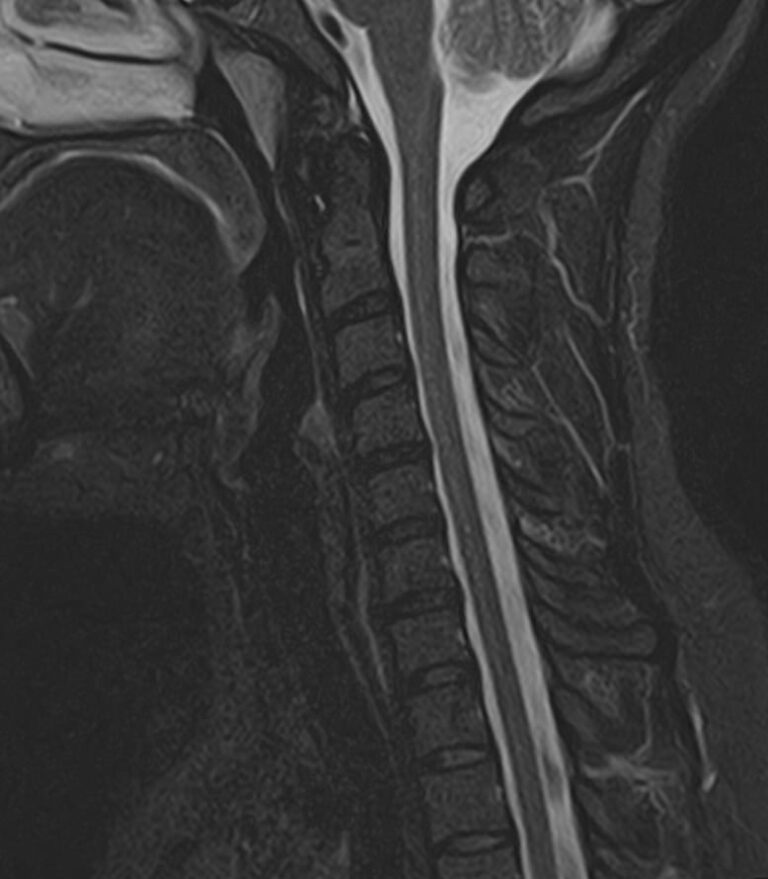

Для того, чтобы оценить состояние шейных позвонков с прилегающими тканями и одновременно визуализировать плечевой сустав, в нашей клинике выполняется комплексное обследование, включающее два протокола: МРТ шейного отдела позвоночника и МРТ плечевого сустава.

Метод МРТ позволяет оценить состояние всех анатомических областей шейного отдела позвоночника: костную структуру позвонков, спинной мозг с отходящими от него нервными корешками и окружающие мягкие ткани. Протокол обследования плечевого сустава включает оценку костной структуры, суставной капсулы, полости сустава с выстилающей его синовиальной оболочкой, связок, сухожилий, мышц и окружающих мягких тканей.